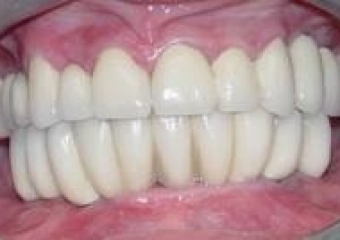

Sorriso final, do caso terminado em Junho de 2006

Imagem Final Intra Oral